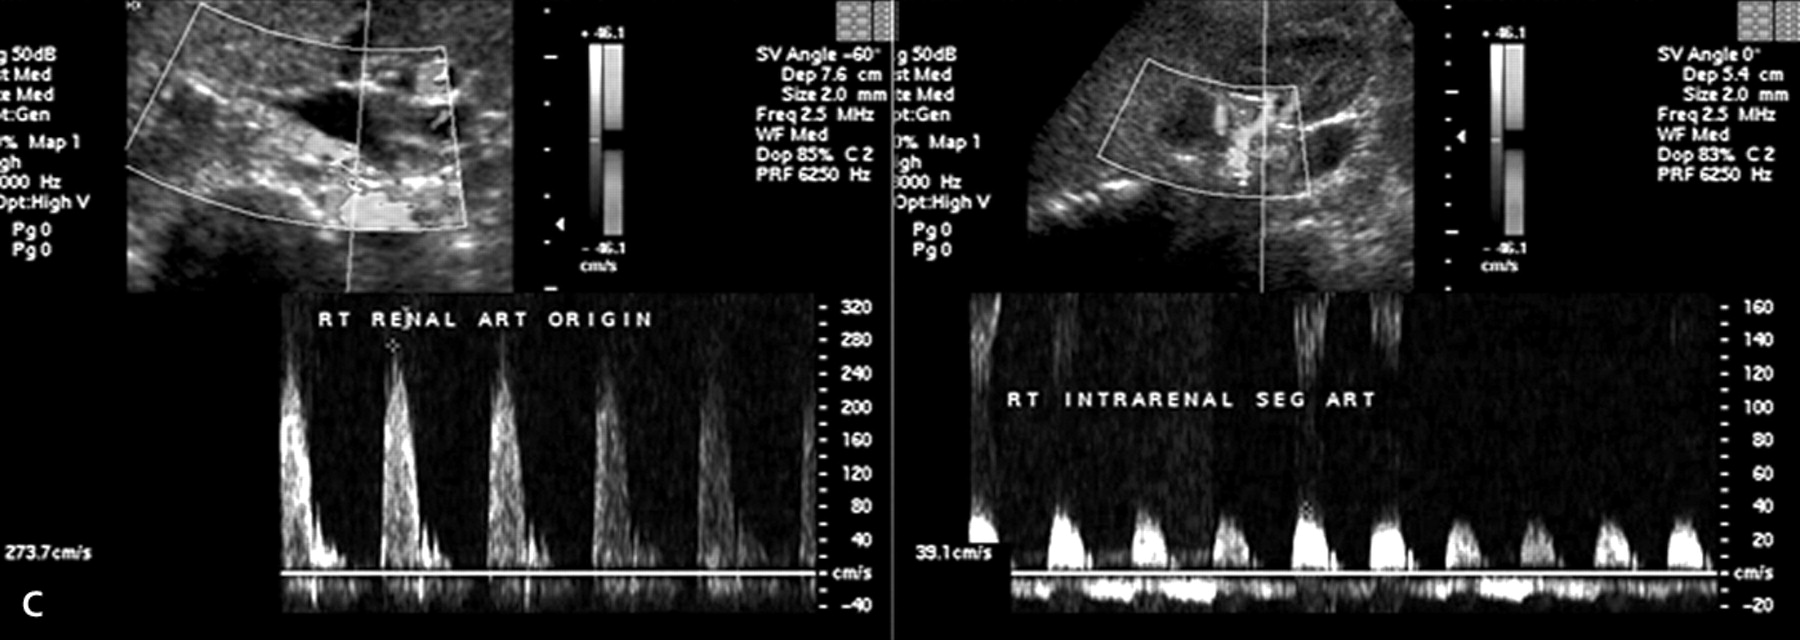

Renal Artery Doppler